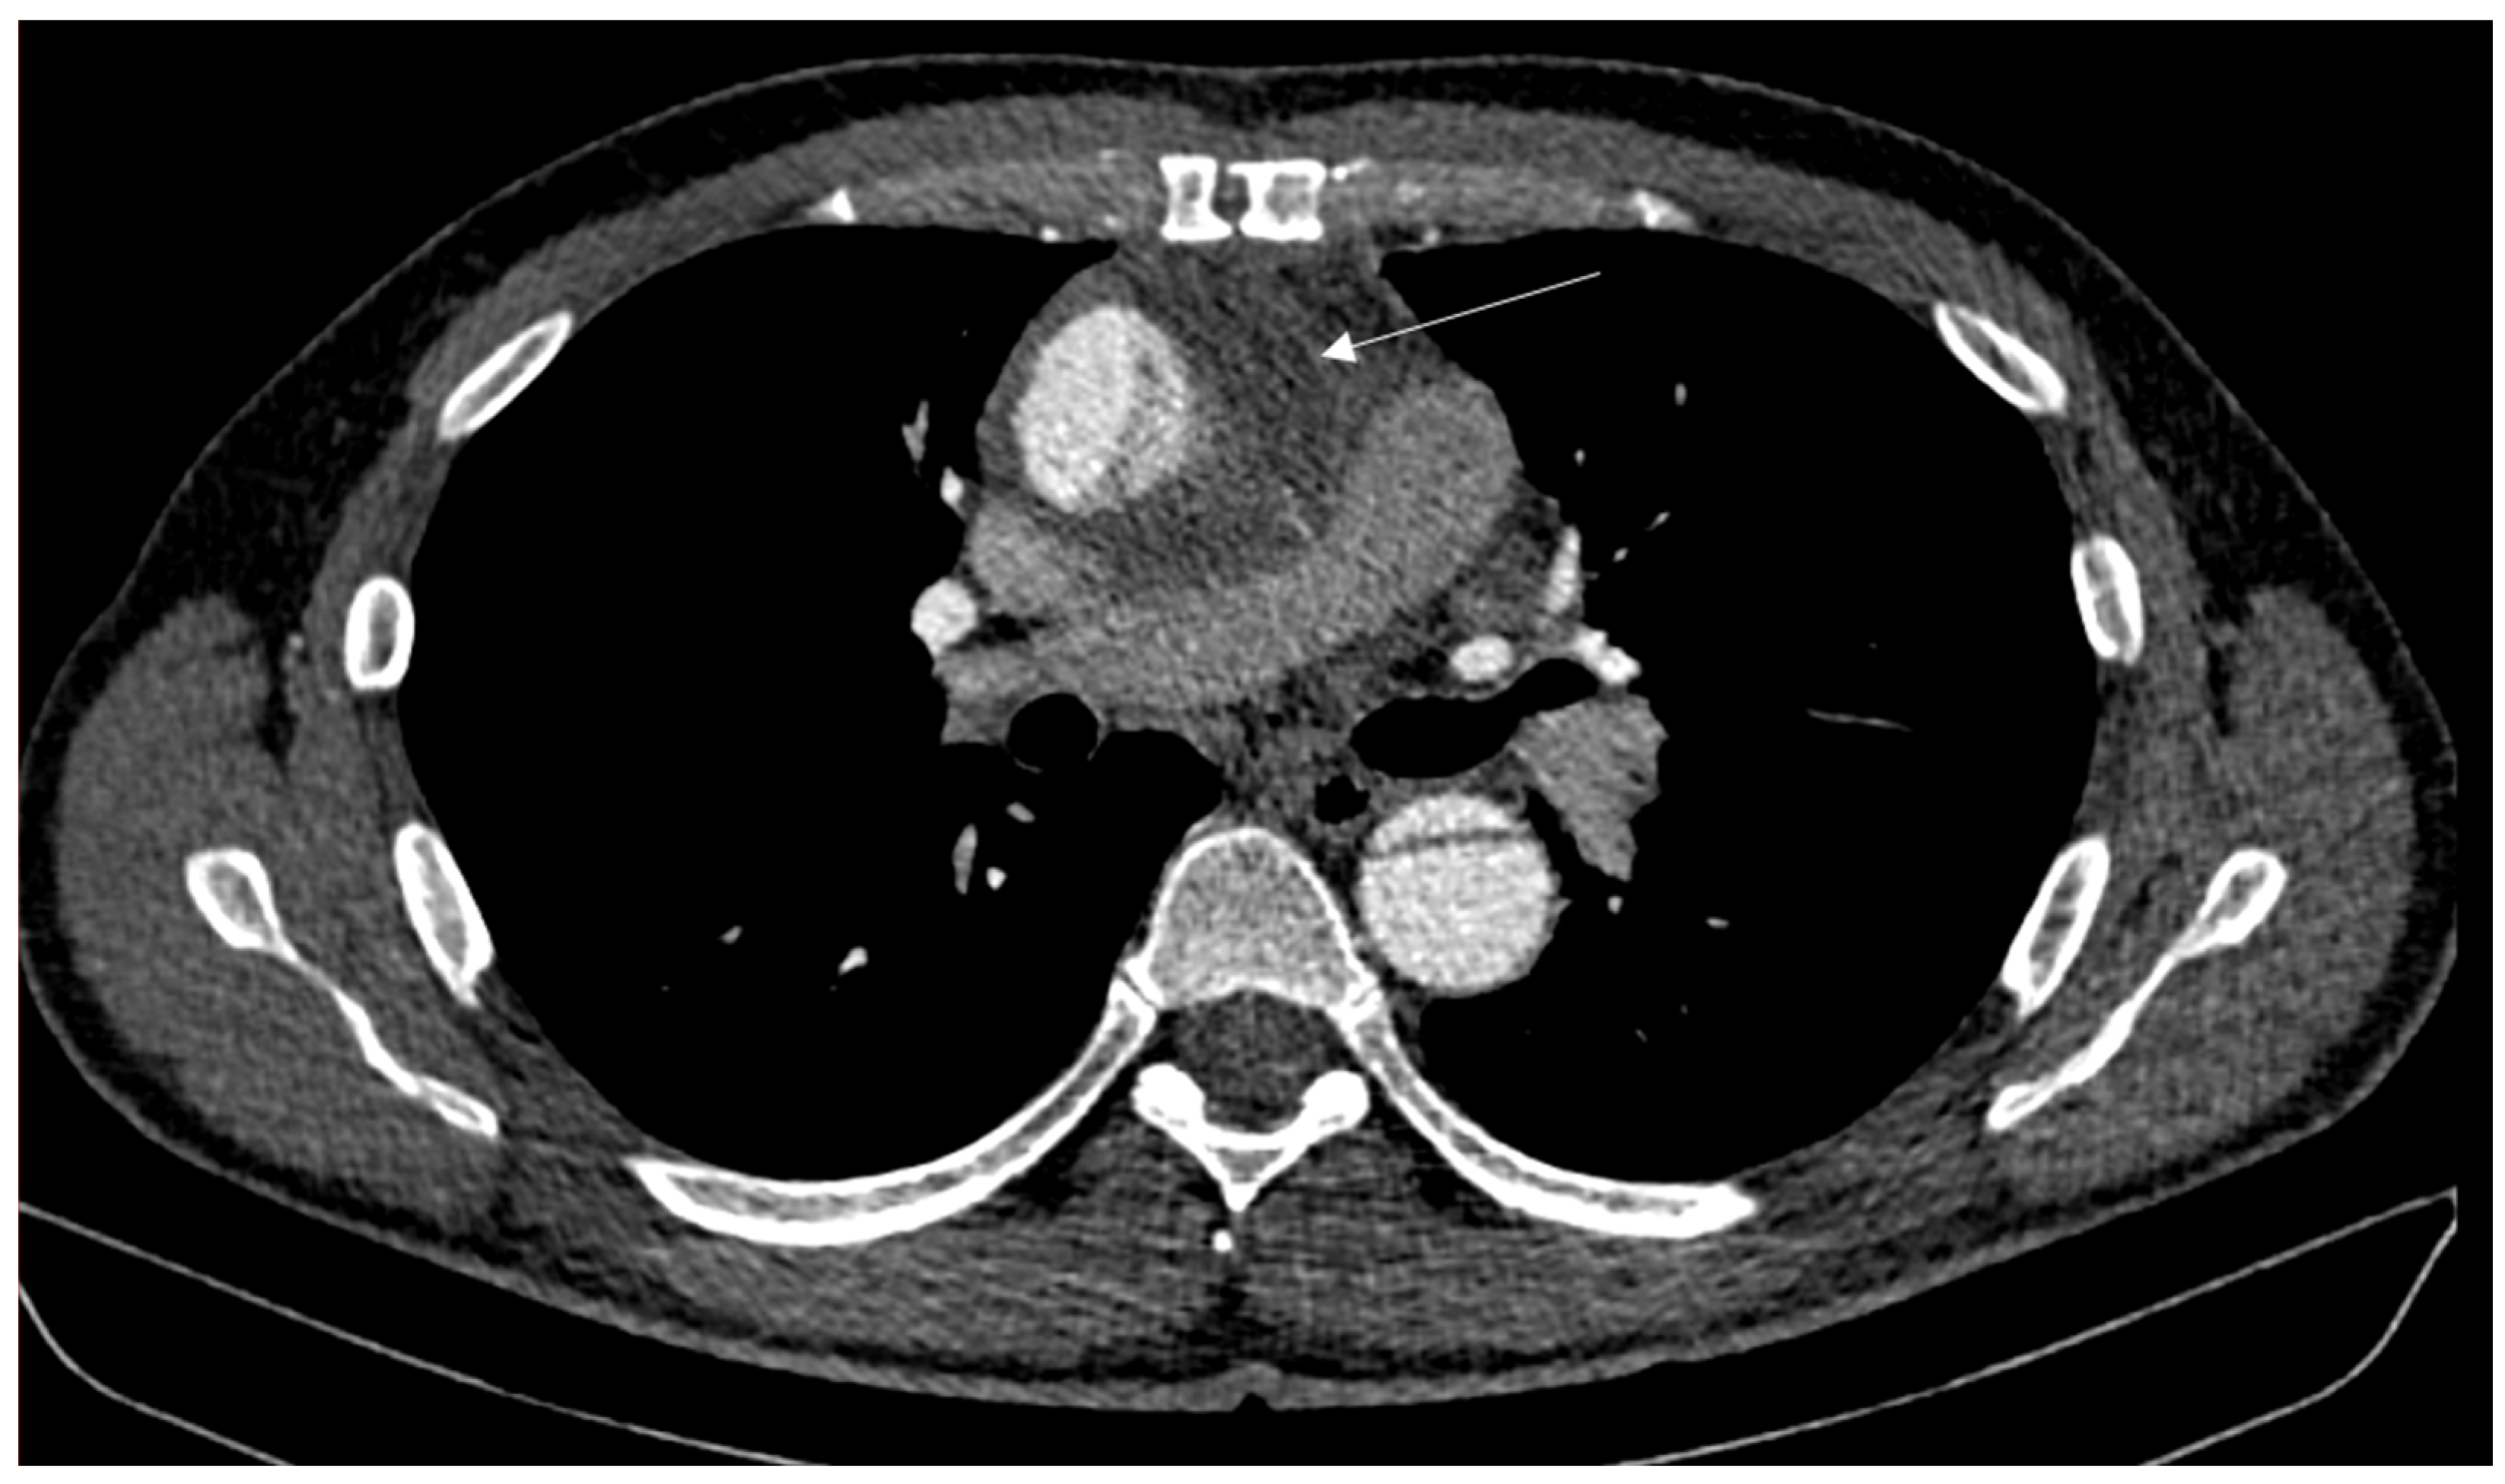

2. Case Report